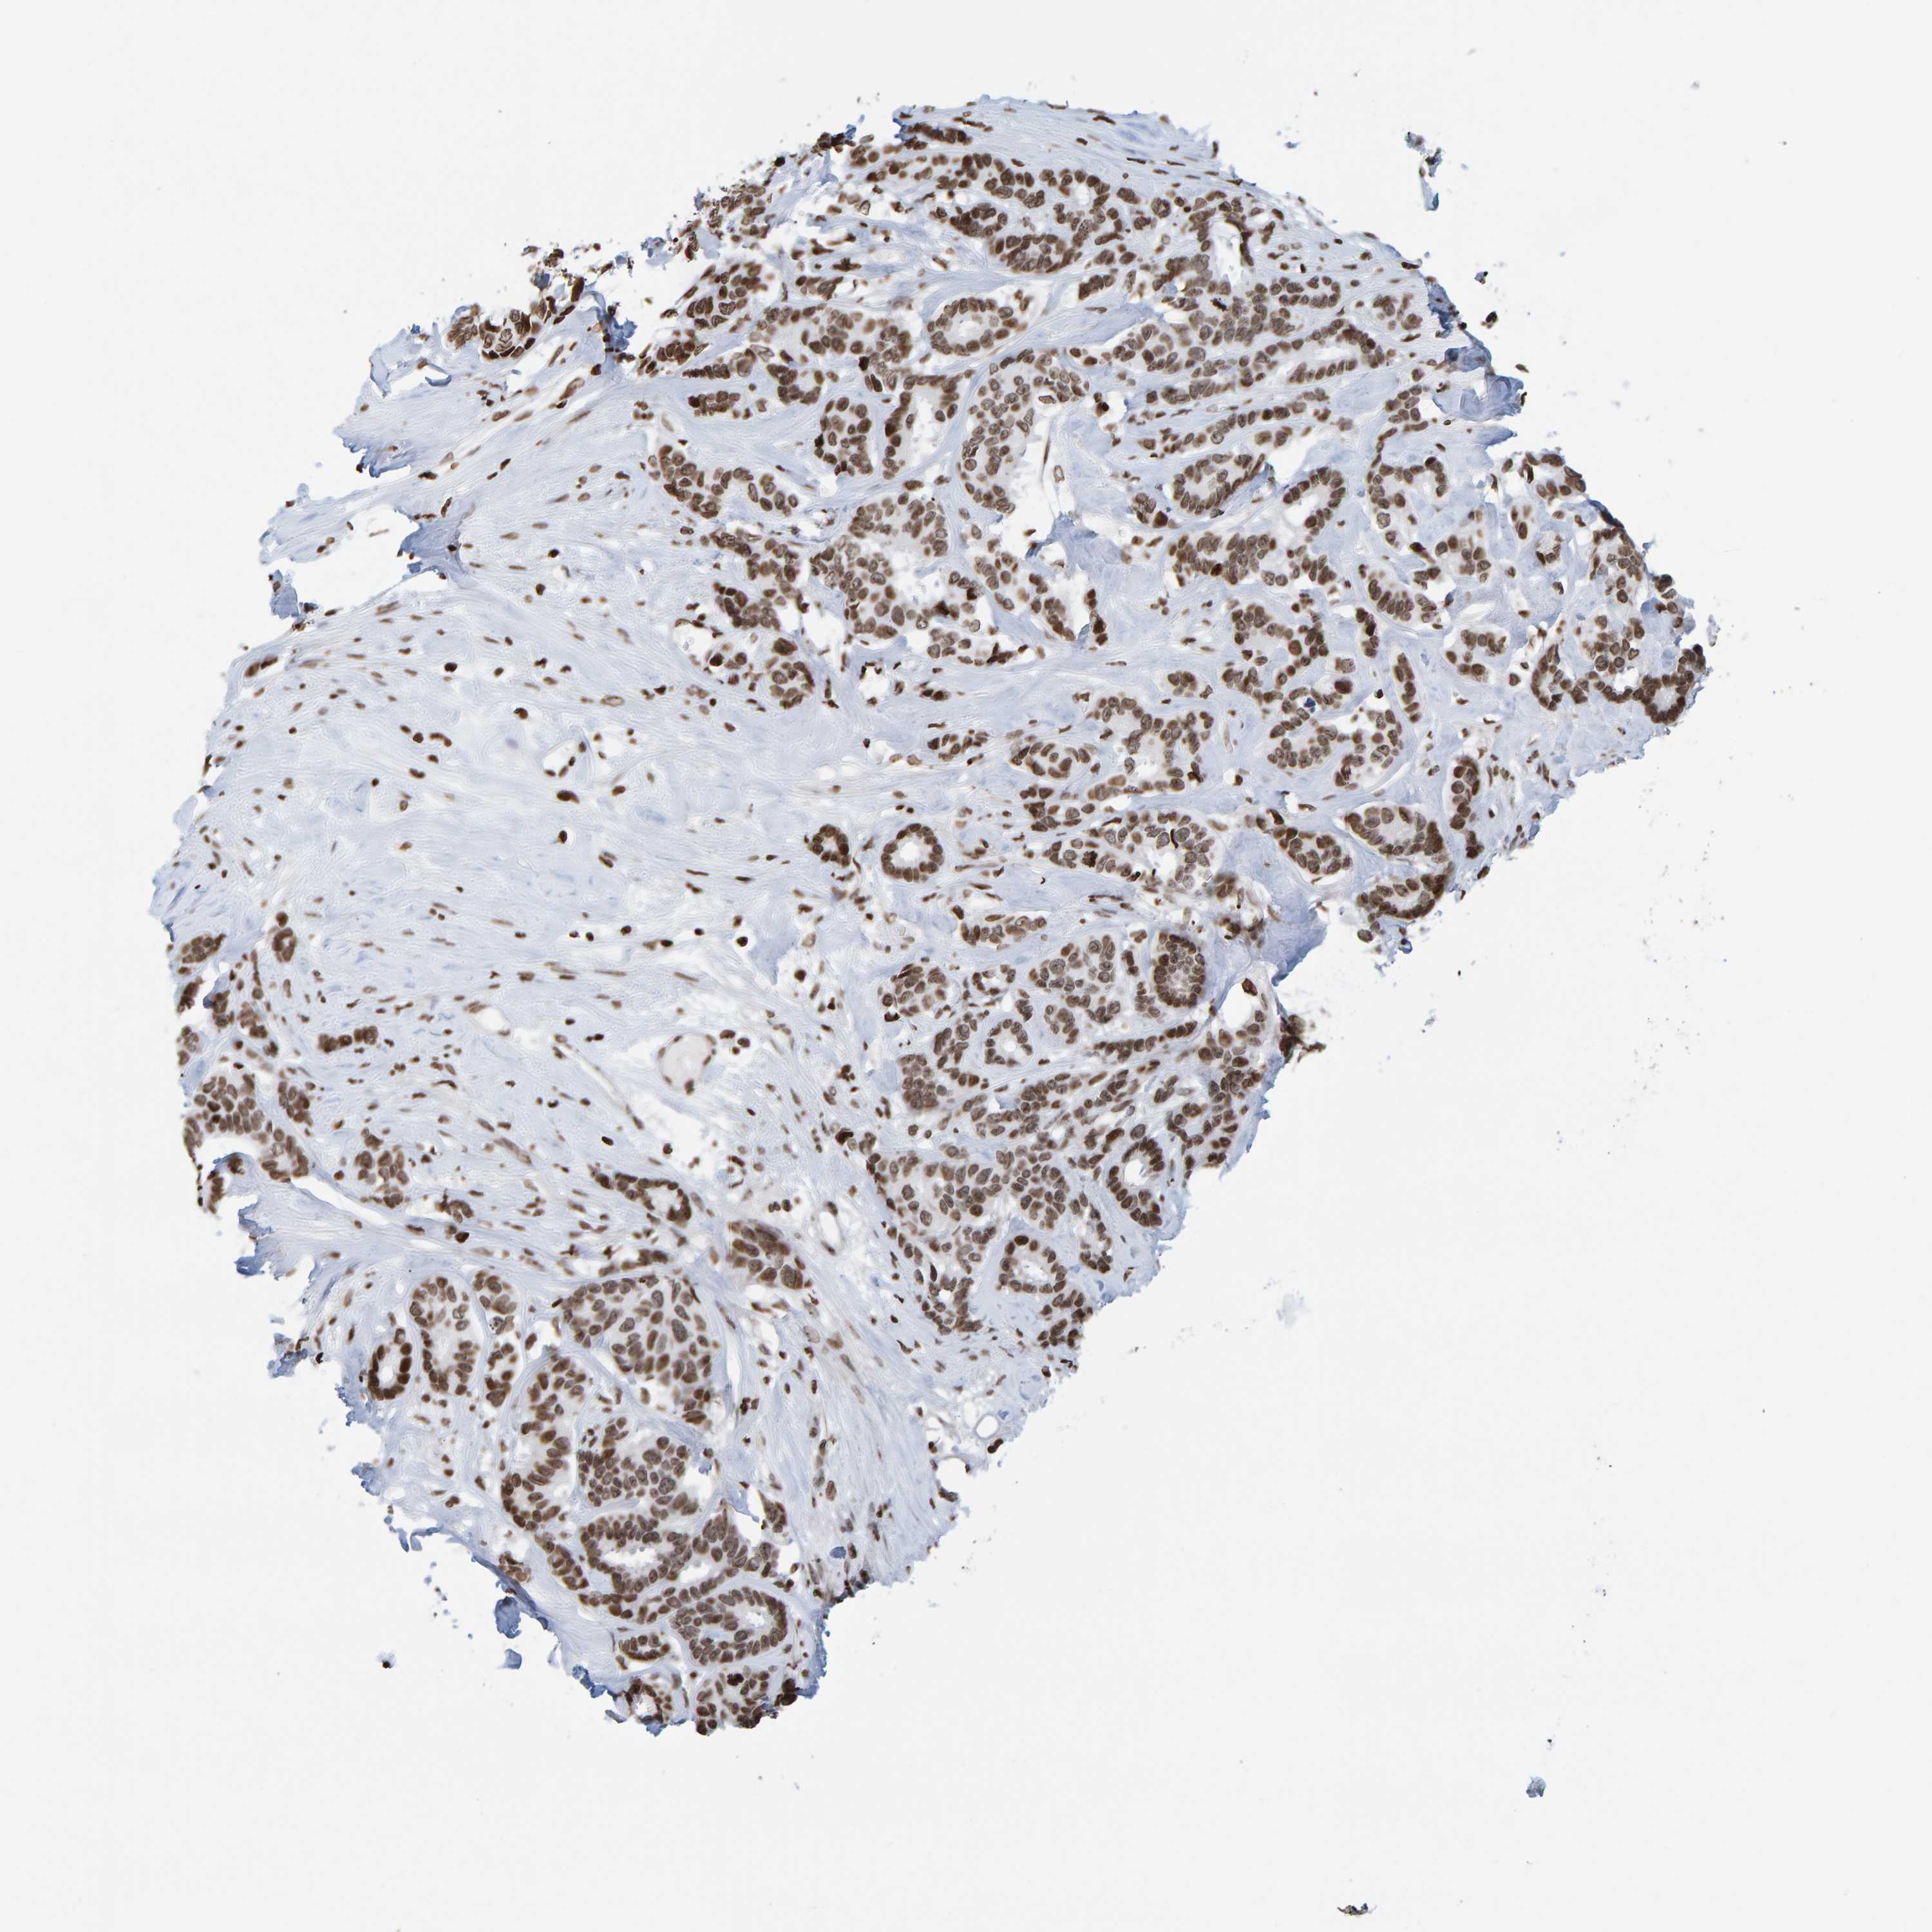

CANCER BREAST CANCER Show tissue menu

BRCA TCGA BRCA VALIDATION PROTEIN EXPRESSION